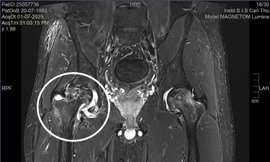

TPO - Điều trị ở Mỹ và Hàn Quốc với chẩn đoán thoát vị đĩa đệm, nam bệnh nhân người Mỹ gốc Việt vẫn không cải thiện được tình trạng đau nhức và đi lại khó khăn. Trở về Việt Nam, anh được các bác sĩ trong nước phát hiện nguyên nhân thật sự là hoại tử chỏm xương đùi và điều trị khỏi bệnh.